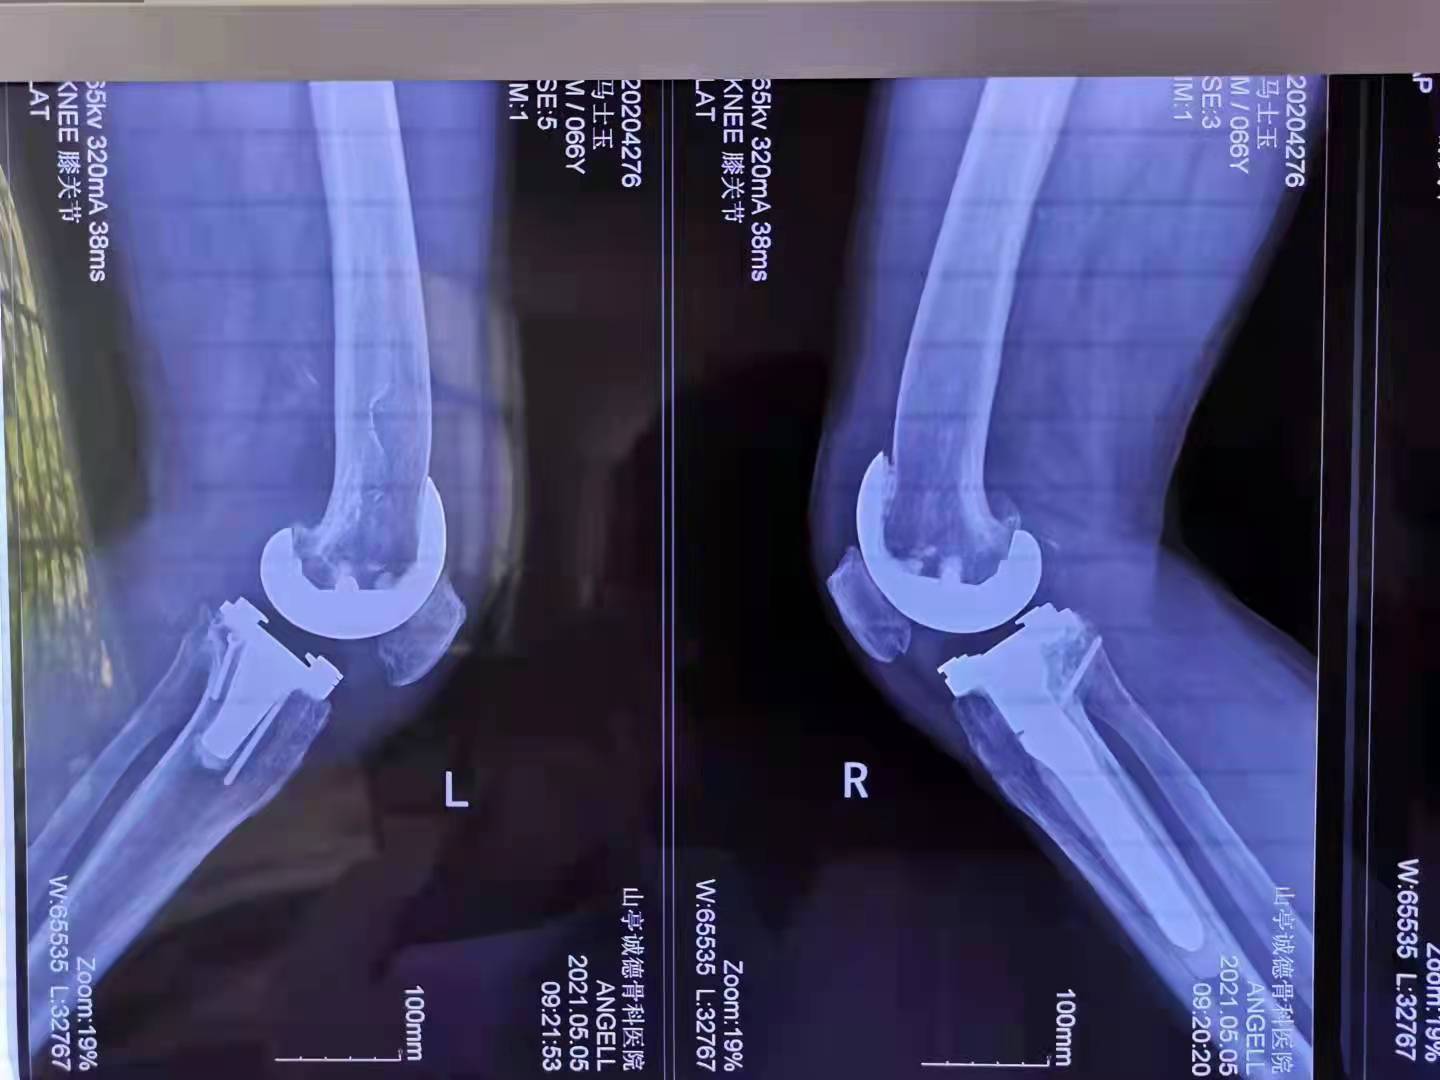

他來到了山亭誠(chéng)德骨科醫(yī)院醫(yī)治,多年的頑疾。讓馬先生本沒抱有任何希望,然而,誠(chéng)德骨科醫(yī)院的李俊鋒院長(zhǎng)及團(tuán)隊(duì)給他帶來了希望,對(duì)這種復(fù)雜的病情進(jìn)行了精心的會(huì)診,制定了詳細(xì)而縝密的手術(shù)方案,予以分期進(jìn)行雙側(cè)膝關(guān)節(jié)置換手術(shù)。

手術(shù)恢復(fù)非常讓人滿意,馬先生已經(jīng)像正常人一樣參加工作,過上了幸福愉快的生活。